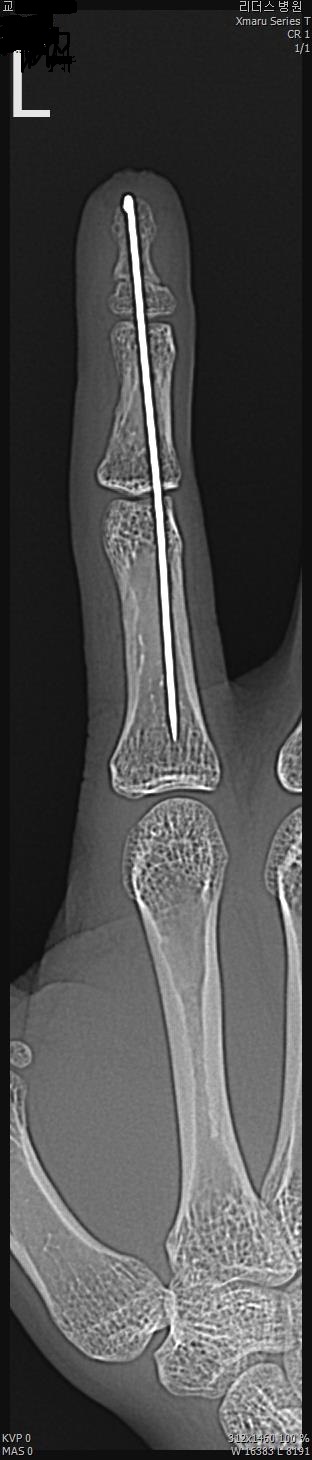

2017년 2월 14일 수지접합 ( 좌측 2수지 절단 치료 전, 후 모습)

2017년도 224일 당시 ( 외국인 교 **)께서 기계에 전달되어 본원 방문함.

올 해 19일 약 1년여간 수지접합 치료 전,후 과정을 올립니다.